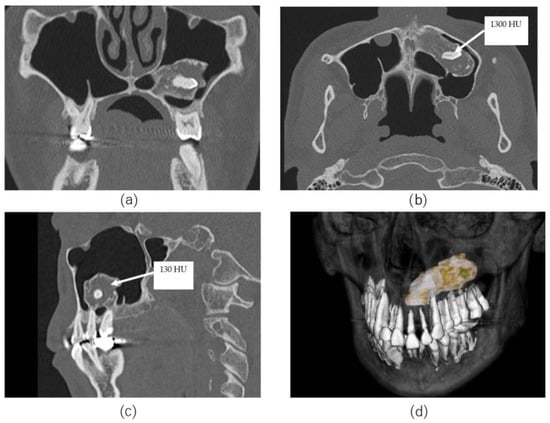

A Unique Case of Supernumerary Teeth Erupting Inside a Maxillary Sinus Osteoma

3. Case Presentation